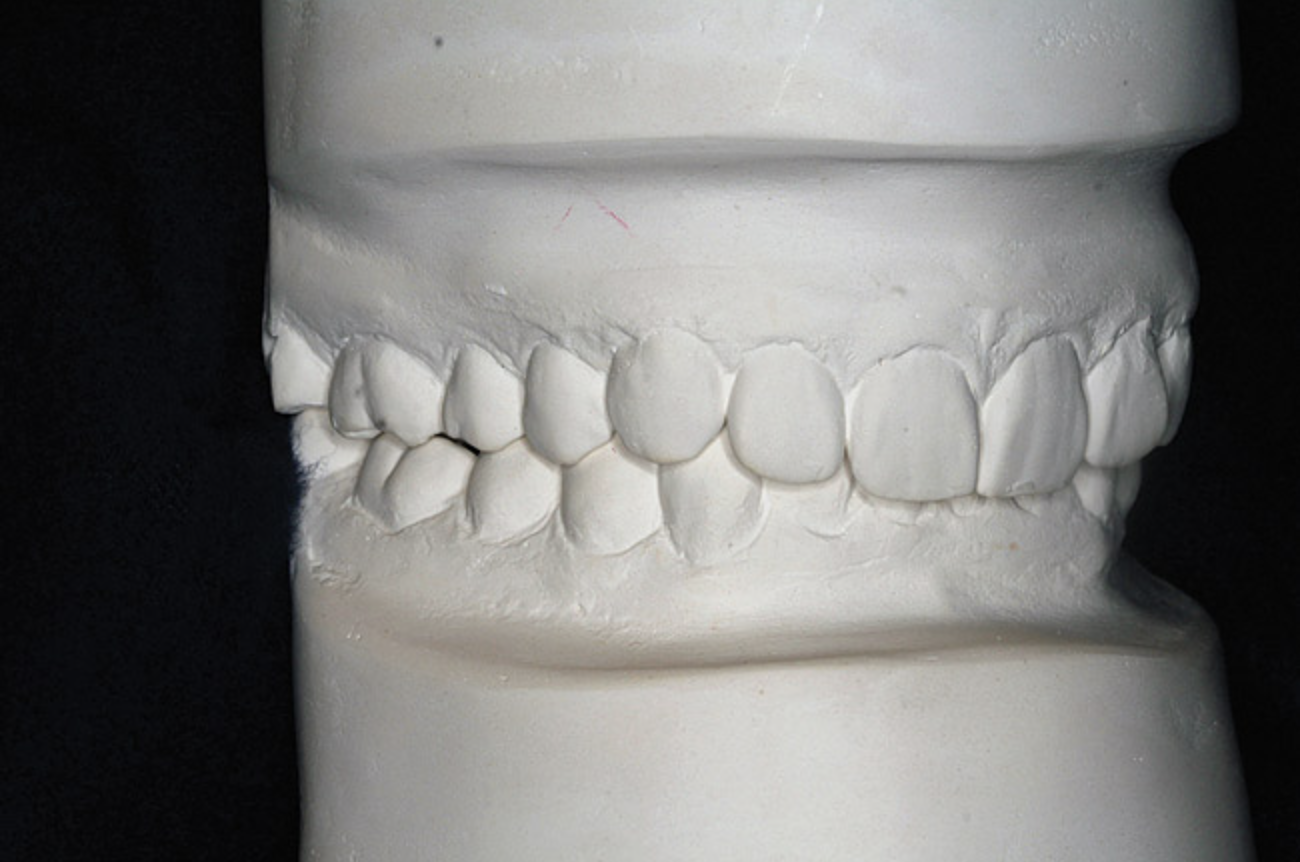

Figure 7B  This case is an example of the importance of evaluating the bite with the joints seated in a stable position. Orthodontic treatment was rendered to correct a "deep overbite" and trauma to the maxillary incisors. B) Handheld models showing correction of the deep overbite after orthodontics has been completed. The patient complained of "jaw" discomfort after orthodontic treatment.

Figure 7B